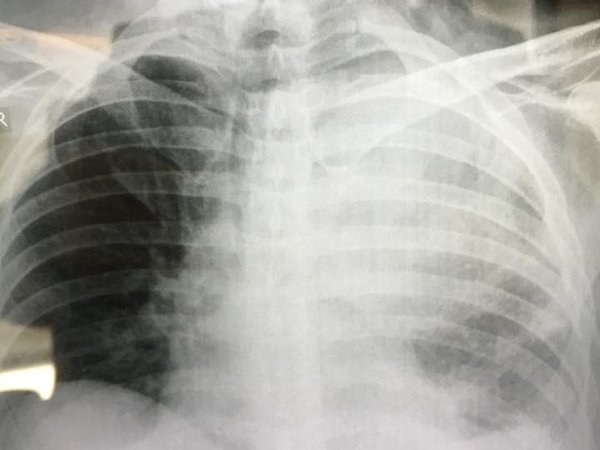

«Αυτές είναι φωτογραφίες από μερικούς καρκινοπαθείς ασθενείς μου.

Με την άδεια του Γιώργου Άστρα, ο οποίος είναι ένα από τα μέλη της εξειδικευμένης επιστημονικής ομάδας της Ογκολογικής Μονάδας στο American Medical Center, αναδημοσιεύουμε τις φωτογραφίες, ενώ παραθέτουμε και μια συμπληρωματική δήλωση του στη CITY:

Δείτε τις πραγματικά συγκλονιστικές φωτογραφίες: